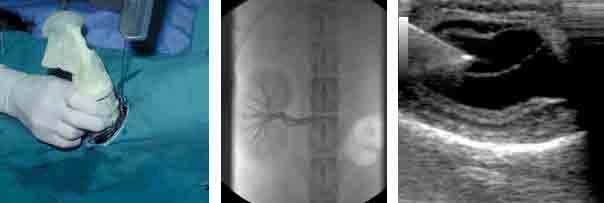

Interventional imaging provides minimally invasive methods of collecting tissue or depositing cells in virtually any organ system. We have extensive experience in interventional procedures with all imaging modalities. The complexity can range from simple collection of fluid or cells to implantation of cells within a fetus to create chimera or place a device within an organ or vessel using an endovascular approach. Biopsies can be collected from both bone and soft tissues. We can also develop instrumentation and methodology for unique procedures.

From left to right: Dog chest radiograph; image of dog prostate with benign prostatic hypertrophy; dog kidney with chronic infection.